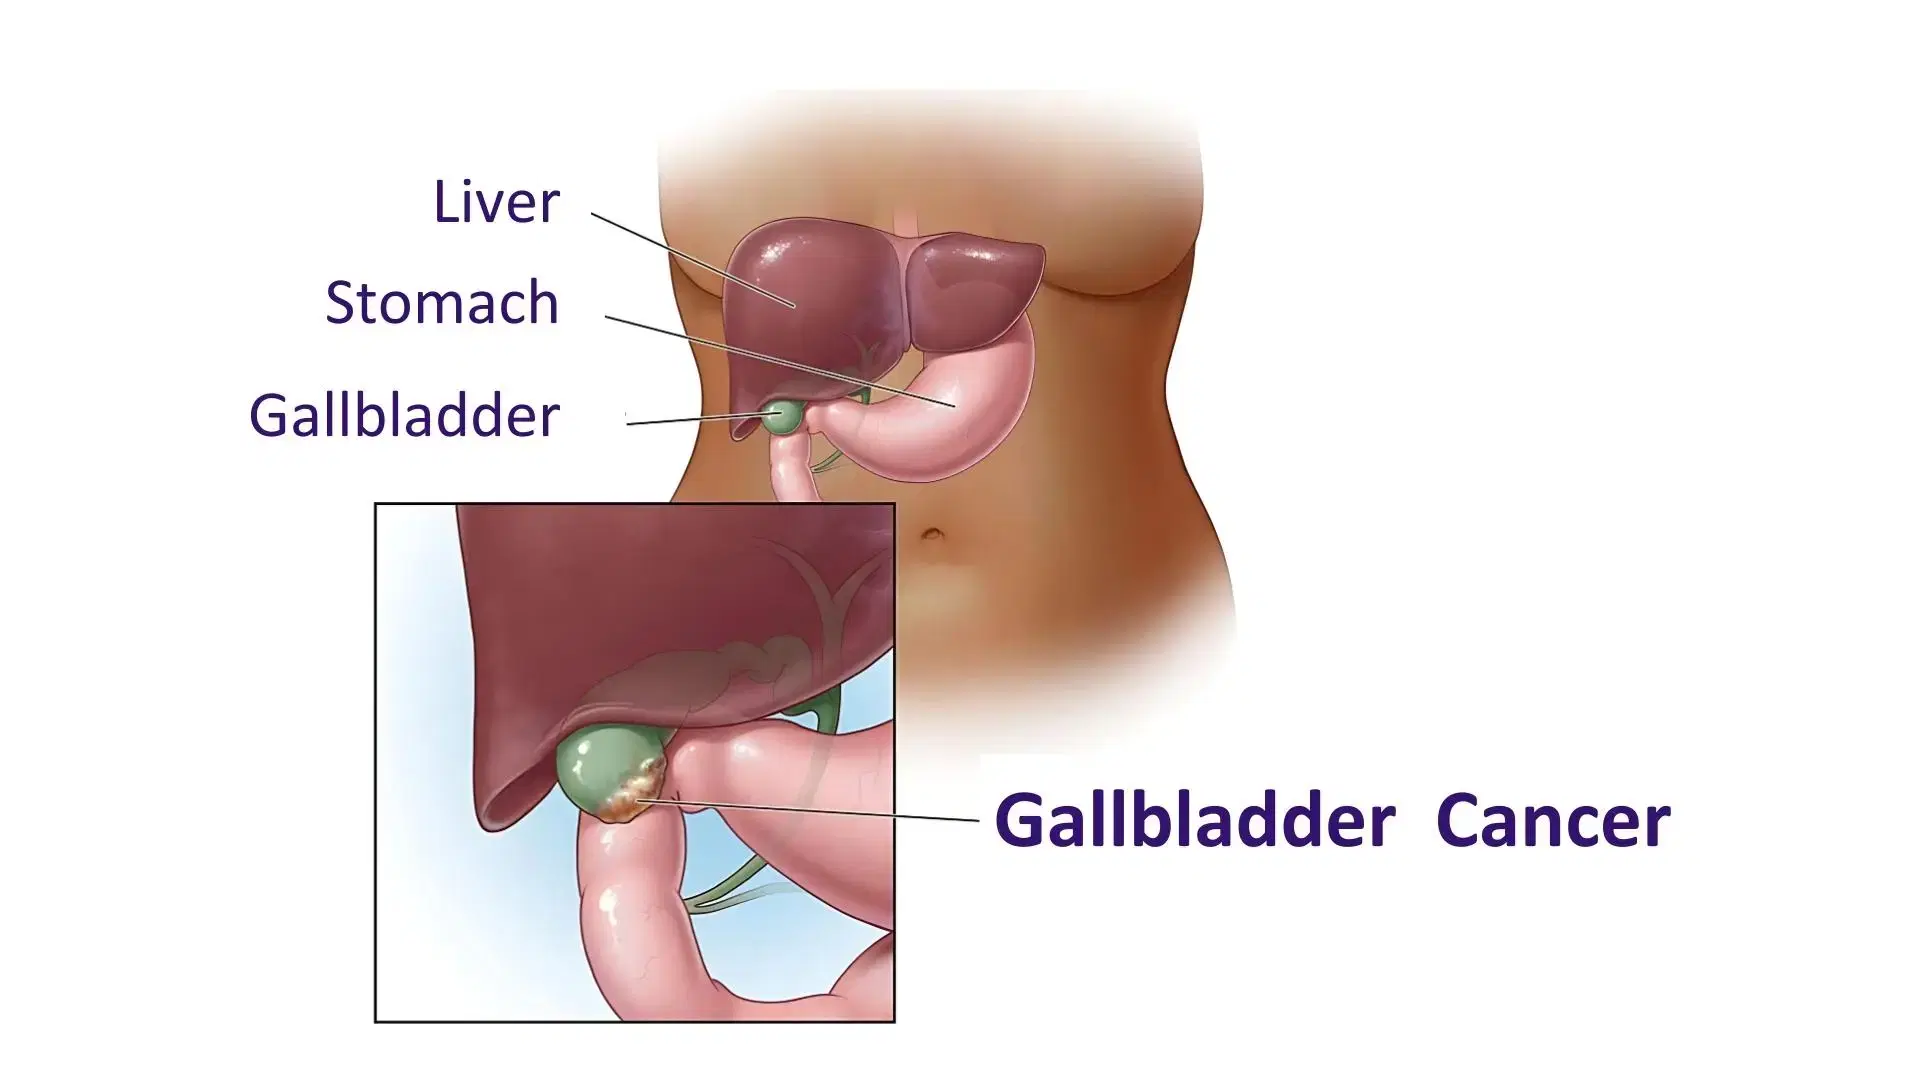

Gall Bladder Cancer in Vijayawada

Gall bladder cancer is a rare but serious condition that often develops silently, making early diagnosis essential. At Vijayawada Gastro Centre, our expert team provides advanced evaluation using ultrasound, CT scans, MRI, and biopsy for accurate detection. Treatment options include surgery, chemotherapy, and targeted therapy, depending on the stage and extent of the disease. Our specialists focus on personalized care to improve outcomes, relieve symptoms, and enhance quality of life. With modern facilities, multidisciplinary expertise, and compassionate support, we offer comprehensive and effective gall bladder cancer treatment for patients in Vijayawada.